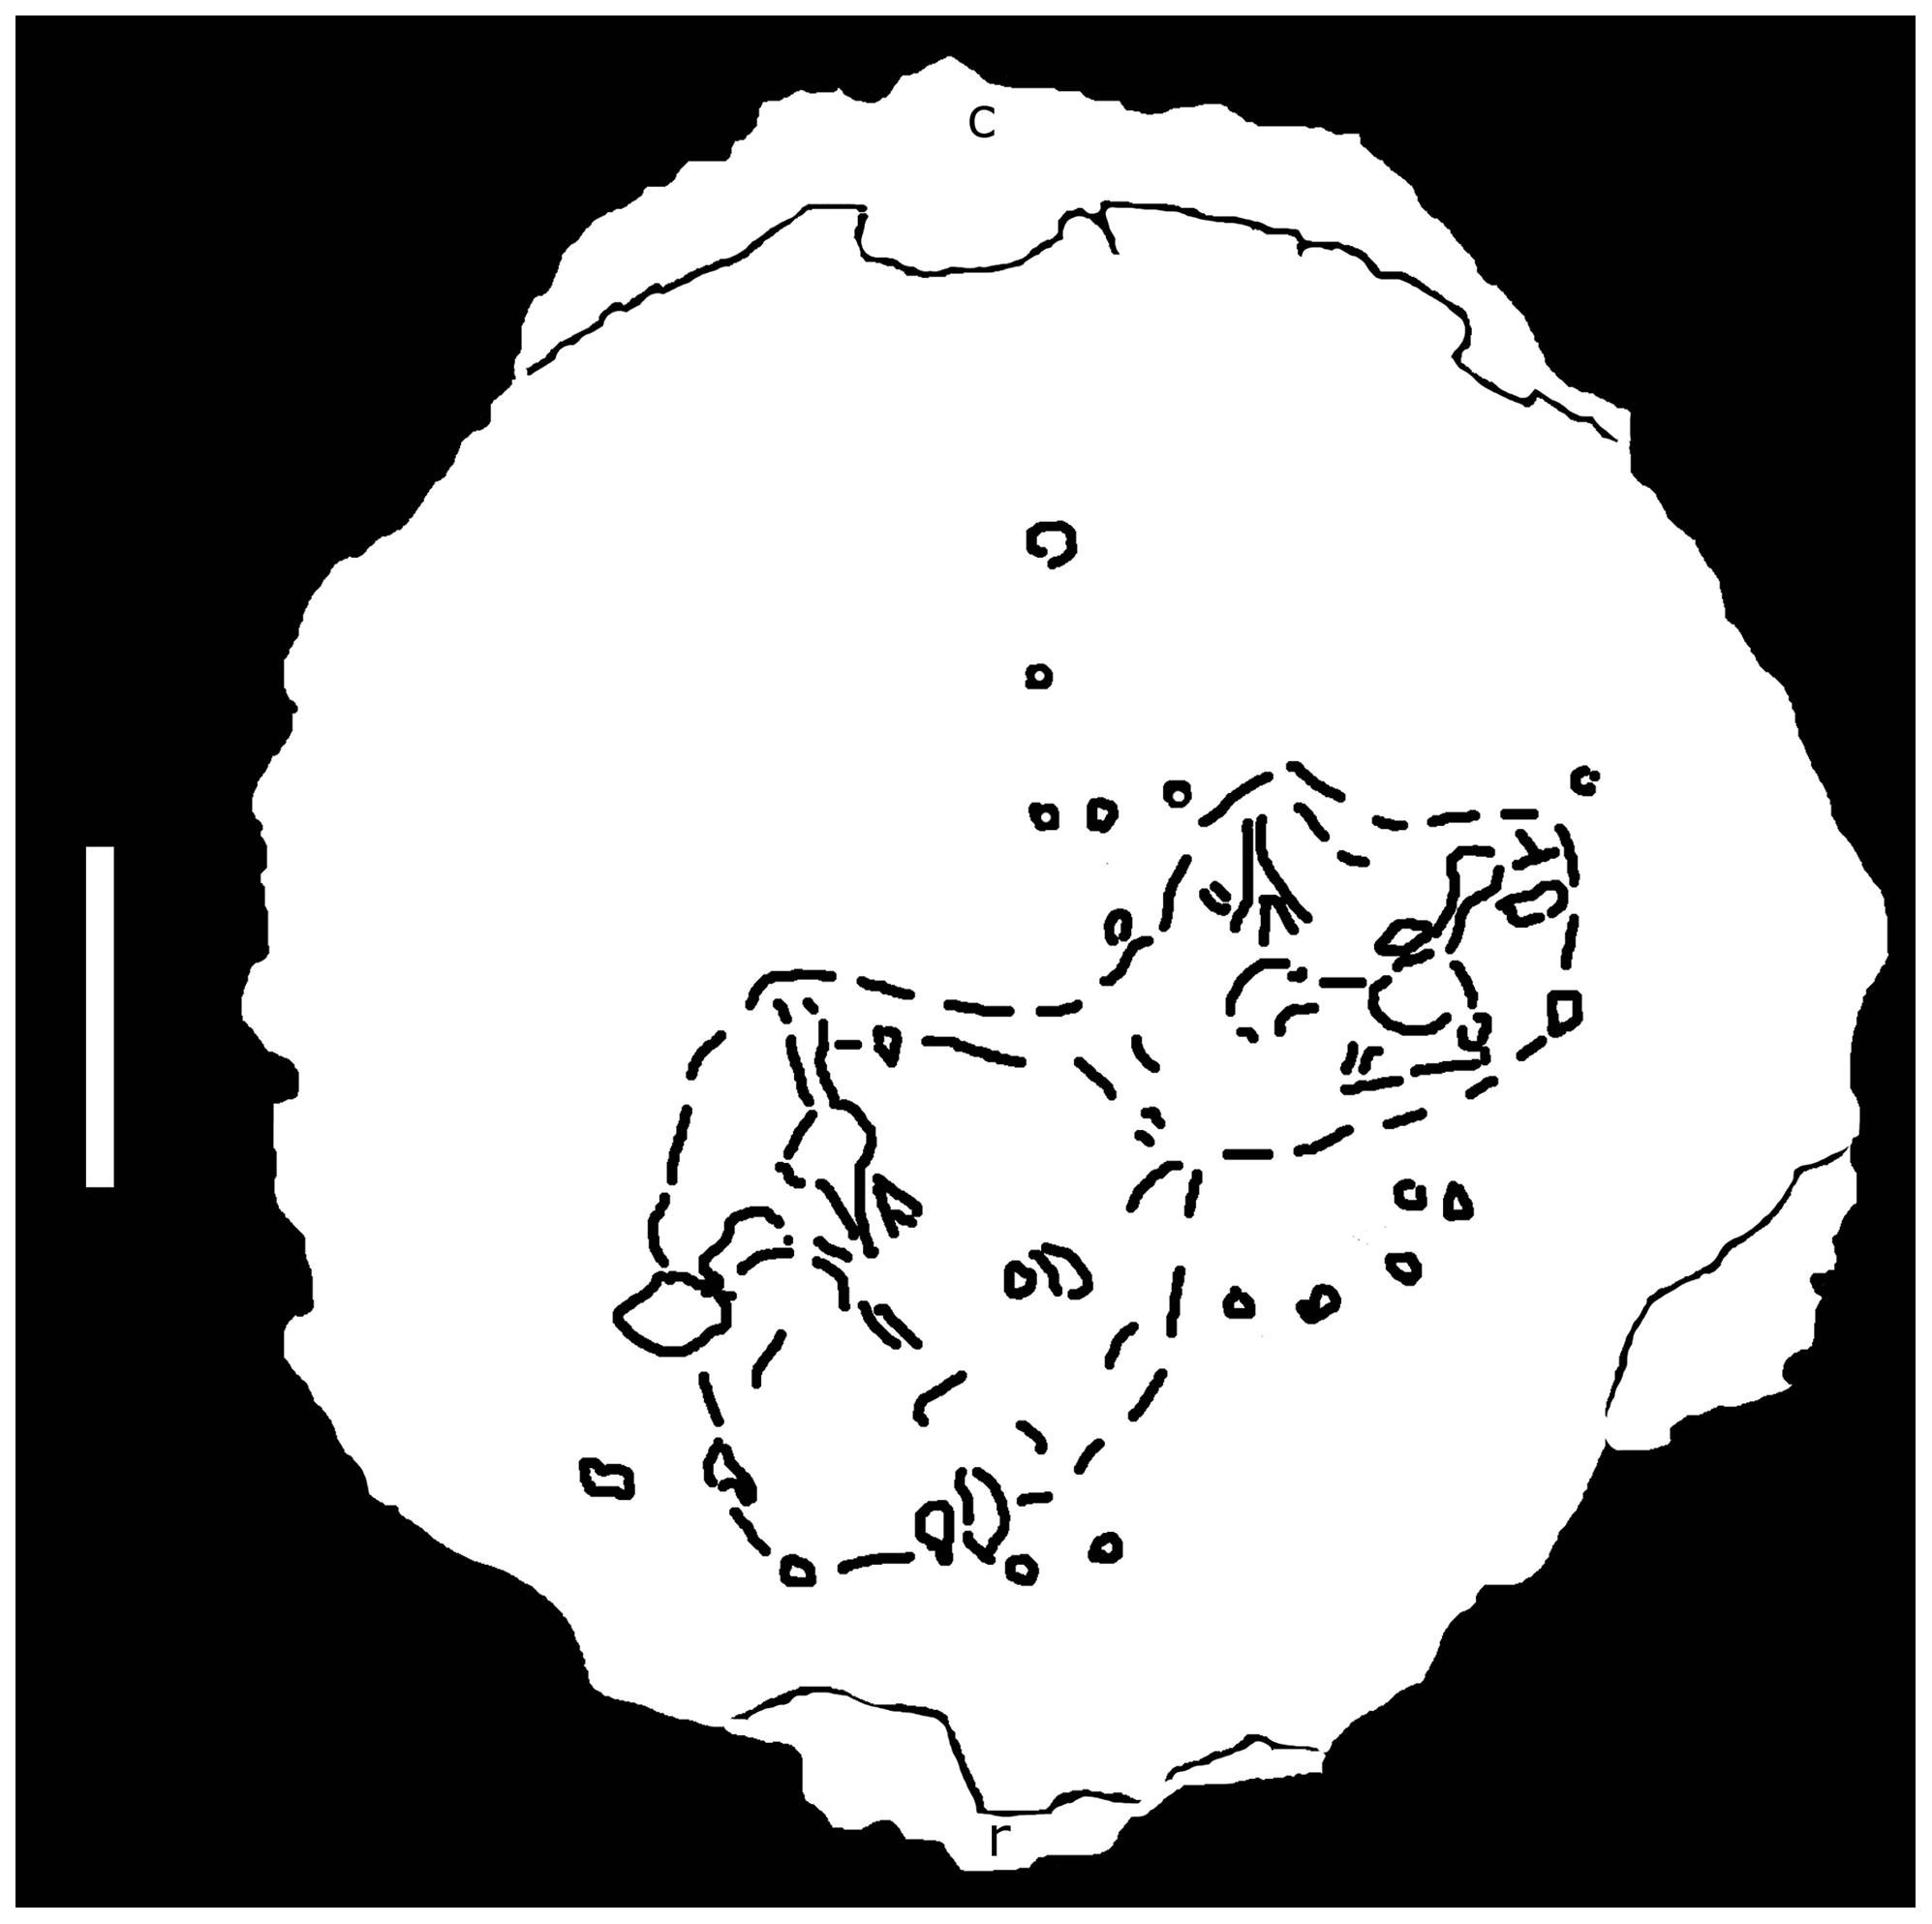

Cranial Pathologies in a Specimen of Pachycephalosaurus

Peterson, J.E. & Vittore, C.P. · PLOS ONE

Primeiro estudo sistemático de patologia craniana em um espécime identificado como Pachycephalosaurus wyomingensis (espécime BMR P2001.4.1 do Museu de Paleontologia Burpee). Peterson e Vittore descrevem duas grandes depressões ovaladas na superfície dorsal da cúpula, acompanhadas de inúmeras cavidades circulares. Tomografia computadorizada revela que as lesões penetram profundamente o osso. A análise comparativa com aves modernas com traumatismo craniano por infecção indica que as estruturas são lesões patológicas resultantes de ferimento traumático seguido de osteomielite secundária. O estudo fornece evidência física direta de que a cúpula de Pachycephalosaurus sofria danos compatíveis com combate agonístico, estabelecendo o alicerce para o trabalho mais amplo de Peterson et al. (2013).

Distributions of Cranial Pathologies Provide Evidence for Head-Butting in Dome-Headed Dinosaurs (Pachycephalosauridae)

Peterson, J.E., Dischler, C. & Longrich, N.R. · PLOS ONE

Estudo definitivo sobre o comportamento de choque de cabeças em pachicefalossaurídeos, baseado na análise sistemática de 109 cúpulas cranianas de espécimes adultos. Peterson, Dischler e Longrich encontram que 22% dos espécimes adultos com cúpula desenvolvida apresentam lesões patológicas concentradas no ápice da cúpula, compatíveis com osteomielite crônica resultante de traumatismo repetido e infecção secundária. Formas de cabeça plana, interpretadas como juvenis ou fêmeas, não apresentam patologias. O padrão de distribuição das lesões, a composição de osso fibrolamelado com fibroblastos capazes de remodelação rápida e a comparação com bovídeos modernos que se combatem sustentam o comportamento de choque de cabeças e/ou flancos como habitual nos pachicefalossaurídeos adultos de cúpula desenvolvida.